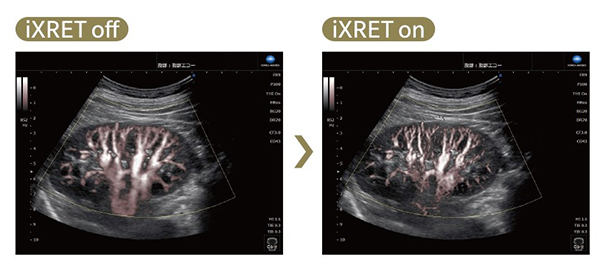

投入した画像処理技術のひとつはiXRET(エクスレット)で,これにより,フレームレートを上げても分解能を落とさずに画像を表示することができる。